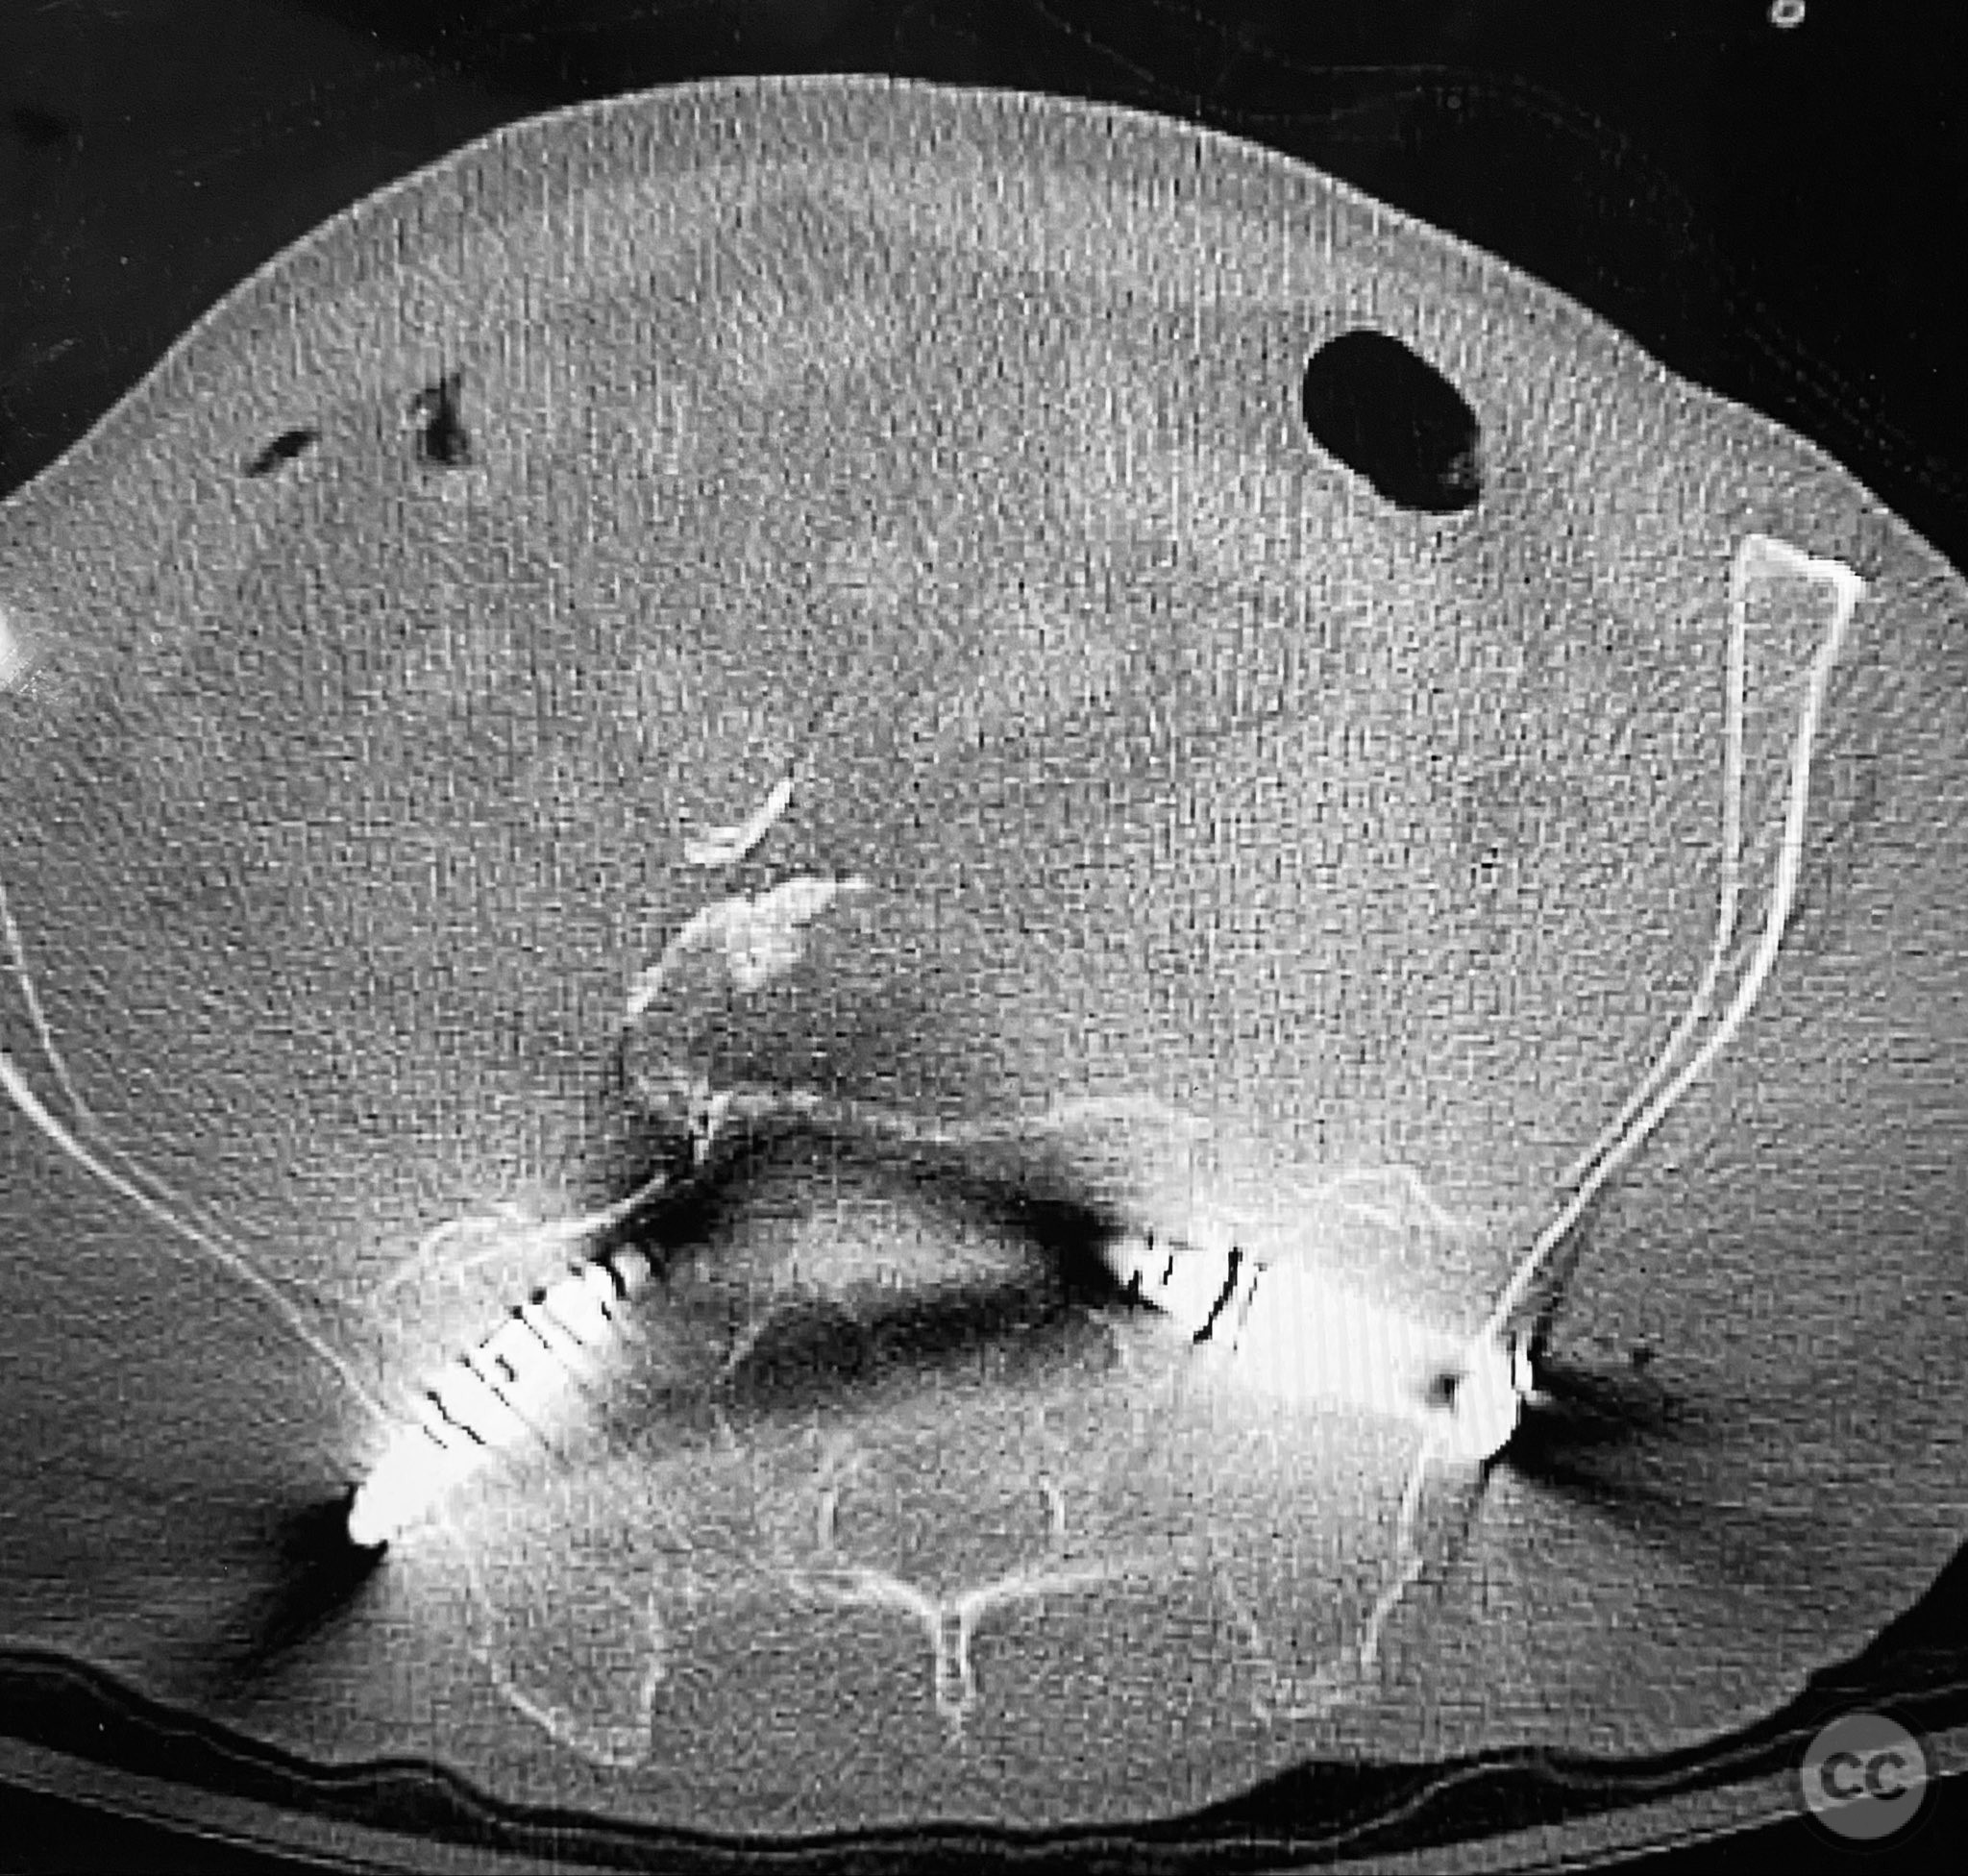

Clinical and radiological findings:  An elderly patient presented with a complex upper sacral fracture characterized by oblique fracture pathways bilaterally, described as a "UYH+pattern" fracture. The patient exhibited compromised bone quality consistent with age-related osteopenia or osteoporosis. Initial clinical assessment prioritized pain control and early mobilization. Radiological evaluation, including computed tomography (CT), confirmed the oblique orientation of the upper sacral fracture lines and their bilateral extension. No neurovascular compromise was reported.

Anatomical surgical approach:  Percutaneous access was established over the dorsal aspect of the pelvis. Small incisions were made lateral to the sacrum, and soft tissue dissection was performed to the level of the os sacrum. Guide pins were advanced under fluoroscopic control along the oblique upper sacral corridors bilaterally. The cannulated CurvaFix device was inserted over each guide pin, articulated to match the oblique fracture pathway, and subsequently locked in situ according to the manufacturer’s specifications.

The articulated nature of the CurvaFix device allowed precise accommodation of the complex oblique upper sacral fracture pathways bilaterally. Percutaneous technique minimized soft tissue disruption and surgical morbidity. Postoperative CT imaging confirmed satisfactory device placement and fracture reduction. The achieved stability provided immediate pain relief, reduced or eliminated narcotic requirements, and enabled early mobilization. Surgeons with experience in device removal have reported no technical difficulties.